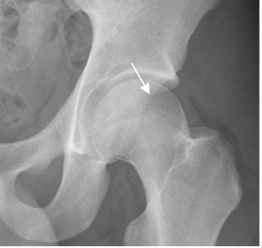

Fig 98. Pinzamiento tipo pincer. Signo del cruce.

Rx AP. Cruce del borde anterior y posterior, antes del borde lateral.